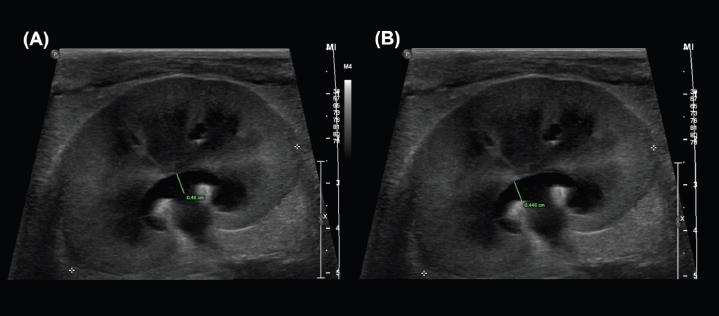

The greatest overall interobserver agreement was achieved by standardized measurements between the renal crest and proximal ureter in the dorsal (DCU) and transverse (TCU) planes (Figs. 2a and b), even though anatomical definitions of the ‟ureteropelvic junction” are lacking in the veterinary and human medical literature (Stringer and Yassaie, 2013). One review of literature examining normal human kidneys concluded that a discrete pyeloureteral junction might not be present, and that in most individuals there might be a gradual zone of transition between the pelvis and ureter. Similar studies are lacking in the veterinary literature. While the unipyramidal morphology of the feline kidney differs from that of the multipyramidal kidney in humans, the embryological development is comparable (Hyttel et al., 2010), and a similar ‟pyeloureteral region” might also be expected in these patients. The ambiguous definition of the pyeloureteral junction might have less impact on interobserver agreement in specific images, however, if the angle of insonation is not perfectly centered and parallel to the long-axis of the proximal ureter. In this scenario, the medial cortical parenchyma or adjacent hilar fat may appear as a discrete, faint echo at the medial aspect of the collecting system due to slice thickness artifact. These echoes could provide a ‟pseudo-margin” for calliper placement, which could increase interobserver agreement. We attempted to minimize the effects of these phenomena by providing clear instructions and allowing the observers to reject images that they considered inappropriate for interpretation in a clinical setting. Our results, therefore, likely reflect the standard that would be encountered during retrospective measurement of still images in clinical practice. Furthermore, if a standardized measurement can be performed reliably and found to correlate with or differentiate between clinical entities, it has value as a diagnostic tool. In these circumstances, whether the region measured represents the precise anatomical boundaries of the renal pelvis is not as important as the reliability with which the measurement can be repeated between observers.

Fig. 2. Examples of the DCU (A) and TCU (B) measurement methods, which had the highest interobserver agreement of all methods examined in this study.